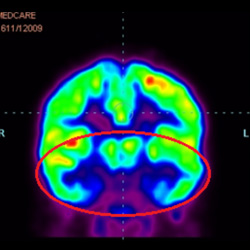

干細胞治療腦癱后改善的客觀放射學證據

細胞治療后,藍色和黑色區域減少,并且看到更活躍的區域。這表明損傷減少并改善了大腦功能。

細胞治療前 PET CT 掃描顯示神經組織中的藍/黑色區域,表明腦癱引起的大腦損傷。

這證明細胞療法是治療腦癱兒童安全有效的方法。細胞療法可以更新大腦損傷的核心,并且可以通過 PET CT 掃描來監測大腦的改善情況。這些細胞療法與標準治療一起促進腦癱兒童的生長和改善。